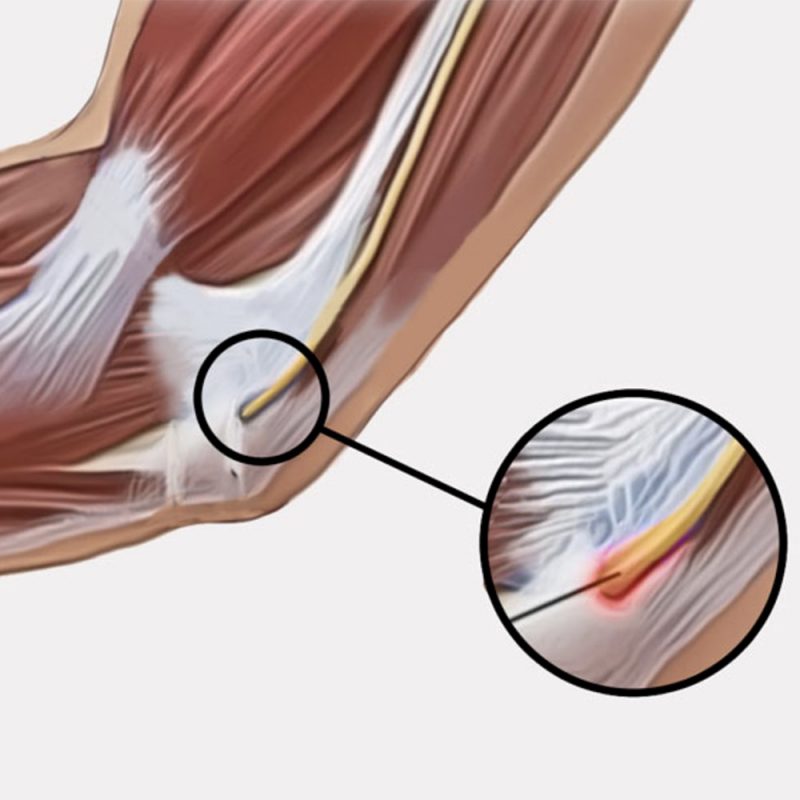

Κατασκευή από ύφασμα τριών στρωμάτων: Εξωτερική επένδυση από αυτοκόλλητο polyamide και εσωτερικά από foam «Unipren» και «Jersey». Ειδικά σχεδιασμένος για τη βελτίωση της ωλένιας νευρίτιδας συγκρατώντας ταυτόχρονα την άρθωση του αγκώνος στην επιθυμητή θέση έκτασης. Φέρει διαμορφώσιμες λάμες αλουμινίου για τον περιορισμό της κάμψης ώστε να ελαχιστοποιείται ο πόνος. Ο νάρθηκας είναι ελαφρύς, δύναται να χρησιμοποιηθεί και κατά την διάρκεια της νύχτας, αποτρέποντας την ακούσια κάμψη του αγκώνος. Στην περιοχή της κοιλότητας του αγκώνος ο νάρθηκας είναι ανοιχτός, για λόγους υγιεινής φροντίδας, και αλλαγής των επιδέσμων χωρίς να αφαιρείται (αν έχει προηγηθεί χειρουργείο). Αμφιδέξιος.

- Ωλένια νευρίτιδα

Κατασκευή από ύφασμα τριών στρωμάτων: Εξωτερική επένδυση από αυτοκόλλητο polyamide και εσωτερικά από foam «Unipren» και «Jersey». Ειδικά σχεδιασμένος για τη βελτίωση της ωλένιας νευρίτιδας συγκρατώντας ταυτόχρονα την άρθωση του αγκώνος στην επιθυμητή θέση έκτασης. Φέρει διαμορφώσιμες λάμες αλουμινίου για τον περιορισμό της κάμψης ώστε να ελαχιστοποιείται ο πόνος. Ο νάρθηκας είναι ελαφρύς, δύναται να χρησιμοποιηθεί και κατά την διάρκεια της νύχτας, αποτρέποντας την ακούσια κάμψη του αγκώνος. Στην περιοχή της κοιλότητας του αγκώνος ο νάρθηκας είναι ανοιχτός, για λόγους υγιεινής φροντίδας, και αλλαγής των επιδέσμων χωρίς να αφαιρείται (αν έχει προηγηθεί χειρουργείο). Αμφιδέξιος.